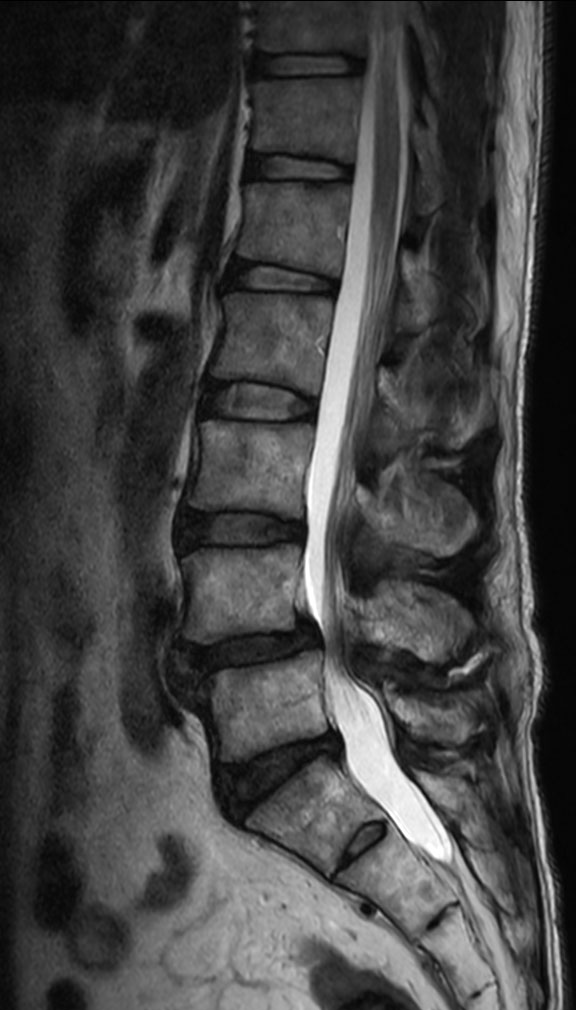

Lumbar Spine disc herniation

Patient with a lumbar spine disc herniation.